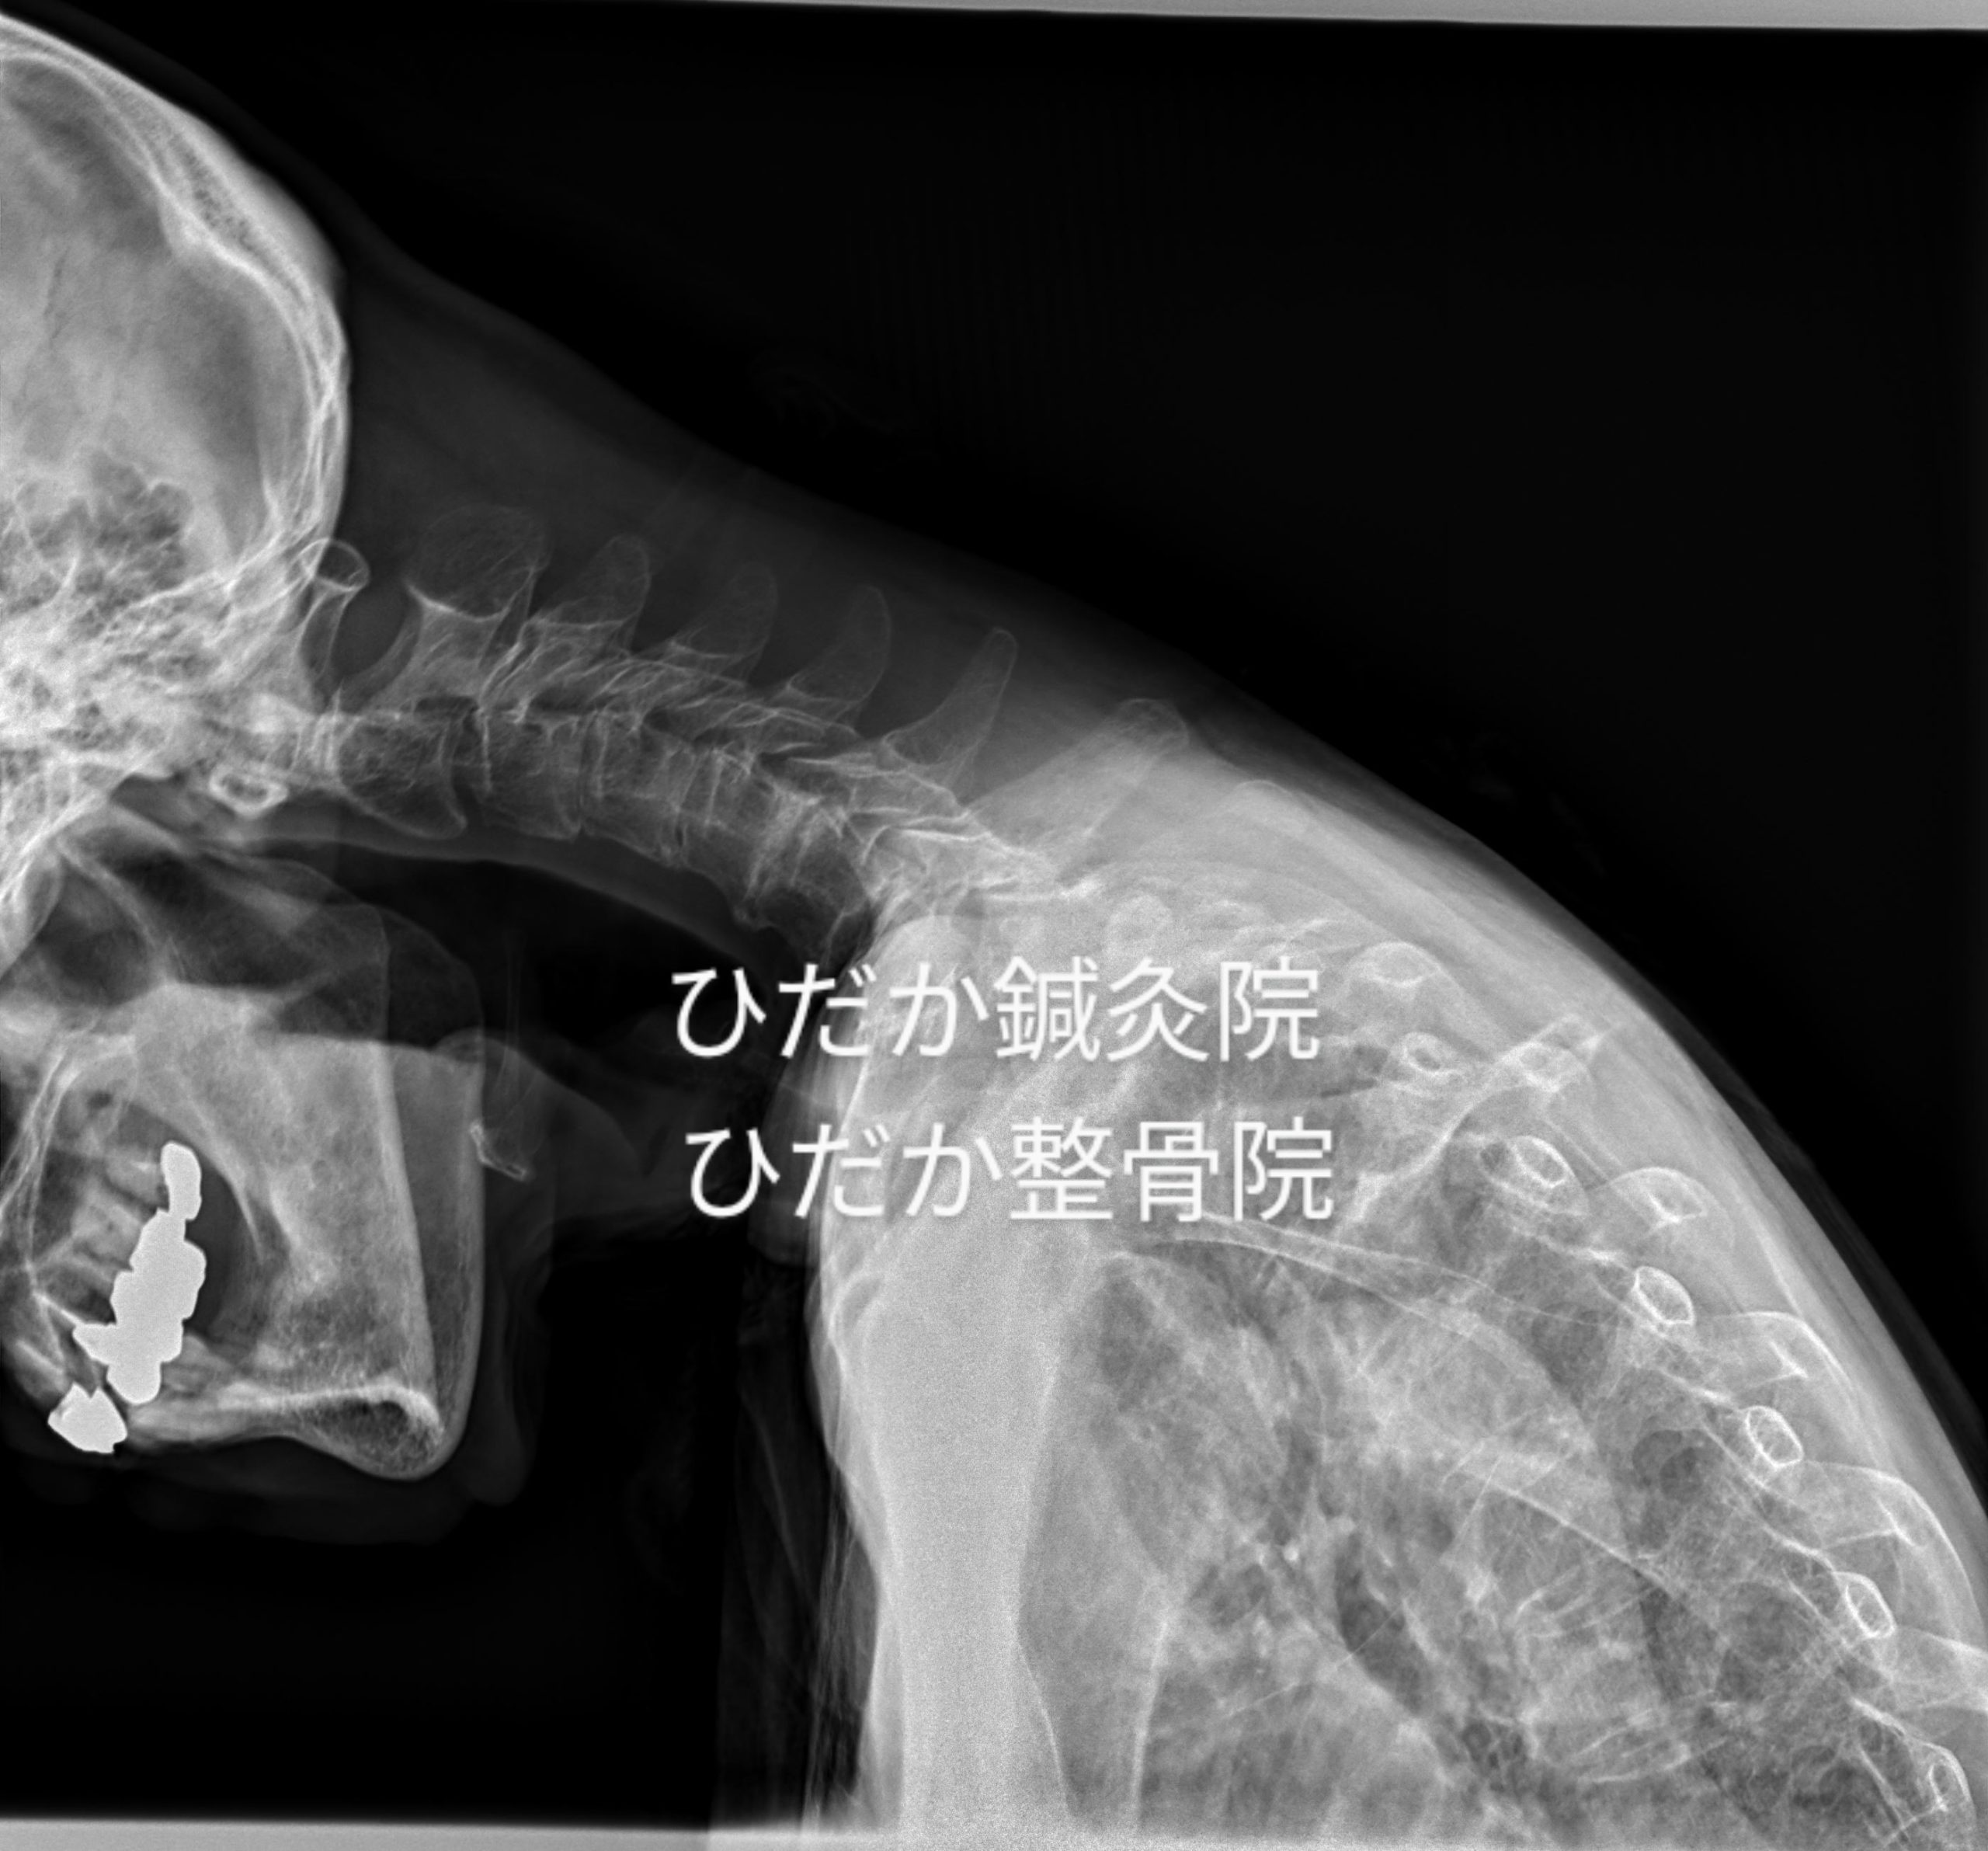

症例 頭・首が下がり前を向けない

久々の投稿は症例です。 77歳女性 介護施設入居後、頭が下がり始め前を向けなくなる。 整形...